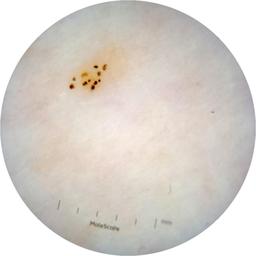

ISIC_6363669

Information

923 x 923

Clinical

Field Value

acquisition_day 264

age_approx 65

anatom_site_1 Trunk

anatom_site_2 Anterior trunk

anatom_site_general anterior torso

concomitant_biopsy False

diagnosis_1 Benign

diagnosis_confirm_type single image expert consensus

family_hx_mm True

image_manipulation instrument only

image_type dermoscopic

lesion_id IL_2591344

patient_id IP_1322385

personal_hx_mm True

sex female